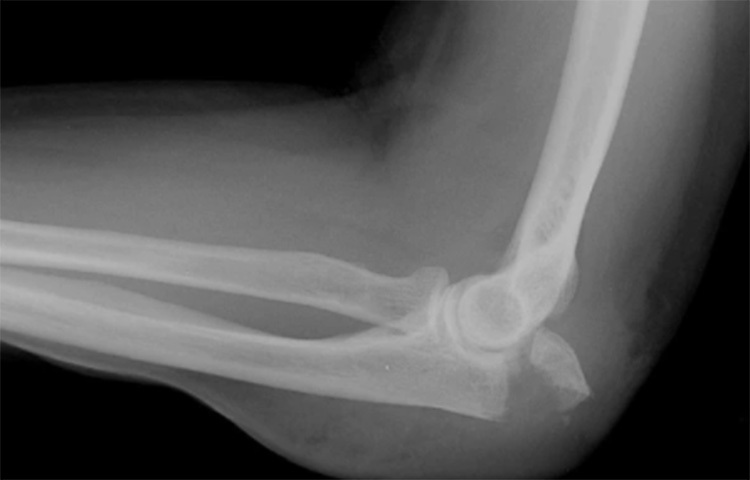

জানা গিয়েছে, কনুইয়ের যেখানে ঠোকা লাগলে এই চিনচিনে ব্যাথা হয়, সেই স্থানের নাম ‘ফানি বোন’। তবে এটি কোনো হাড় নয় বরং একটি স্নায়ু। এটি হাতের প্রধান তিনটে স্নায়ুর একটি। এটি হাতের শুরু থেকে শেষ পর্যন্ত বিস্তৃৃত। এই স্নায়ুর মাধ্যমে আমাদের আঙুলের ডগার অনুভূতি মস্তিষ্কে পৌঁছায়। ‘ফানি বোন’-এর বৈজ্ঞানিক নাম আলনার নার্ভ। এটার অবস্থান ত্বকের কাছাকাছি। ছবি: সংগৃহীত

এই স্নায়ুর অধিকাংশ জায়গাতেই হাড়, পেশি ও চর্বি থাকে। তবে যখন এটি কনুইয়ের নিচের দিকে যায় তখন এটাকে একটি সরু পথ অতিক্রম করতে হয়। যার নাম ‘কিউবিটাল টানেল’। ছবি: সংগৃহীত

ওই টানেলের স্থানে স্নায়ুটির একপাশ কনুইয়ের হাড়ের সঙ্গে যুক্ত থাকে এবং অন্যপাশ আমাদের ত্বকের সঙ্গে। ফলে ওই স্থানে স্নায়ুটি সবচেয়ে বেশি সংবেদনশীল থাকে। ছবি: সংগৃহীত

চিকিৎসকরা জানিয়েছেন, স্নায়ুটি যখন ওই টানেল অতিক্রম করে। তখনই সবচেয়ে বেশি সংবেদনশীল থাকে। তখন কিছুতে আঘাত লাগলে স্নায়ুটি সংকুচিত হয়ে যায়। ছবি: সংগৃহীত